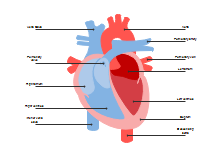

illustrazione scientifica - anatomia umana